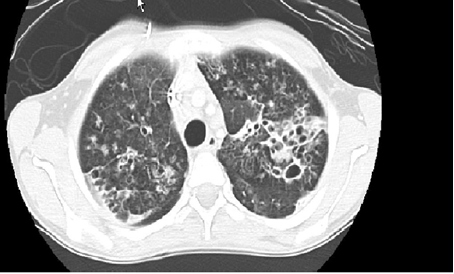

Where available a High-resolution computed tomography (HRCT) scanning is the standard test for diagnosis especially in the absence of characteristic chest radiograph findings of dilated airway, with thickened airway walls. Key features on CT scan: Enlarged internal bronchial diameter with bronchi that appear larger than the accompanying artery. Other findings include the failure of the larger airways to taper while progressing to the lung periphery, air fluid levels in the dilated airways, and the identification of airways in the extreme lung periphery. Other testing may be indicated to diagnose underlying conditions.